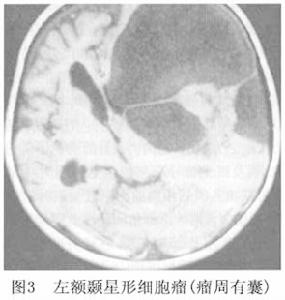

3.CT檢查 纖維型和原漿型星形細胞瘤,因組織含水量達81%~82%,CT多呈低密度,較均勻一致,占位效應不明顯 瘤內無出血灶或壞死灶,瘤周無明顯水腫影。除少數病例外,一般注射造影劑不增強或稍有增強。因腫瘤所在的部位和大小而異,表現相應的占位效應。小腦星形細胞瘤在CT上腫瘤的實質部分呈低(或)混雜密度病灶,造影劑增強後可有輕度增強,而囊腔部分則始終保持低密度影。囊壁部分可呈環形或弧線形增強。腦幹部位的星形細胞瘤CT上可見腦幹的增粗,左右不對稱及出現低密度或混雜密度的腫瘤病灶影, CT顯示腦幹膠質瘤不如MRI理想。部分腫瘤CT上呈等密度,從而使腫瘤在CT上難以發現,此時MRI可明確顯示腫瘤影(圖1)。

4.MRI檢查 星形細胞瘤在MRI上T1W呈低信號 T2W呈高信號。MRI可清楚顯示腫瘤浸潤腦組織的程度。增強後星形細胞瘤一般不強化, 少數腫瘤有周邊斑點狀輕度強化影。良性星形細胞瘤由於腫瘤的生長,使腫瘤內外水分增多,造成T1和T2延長 表現T1加權像呈低信號,T2加權像呈高信號(圖3),信號強度均勻,瘤周水腫輕微,注射Gd-DTPA增強不明顯。隨著腫瘤的生長,瘤內發生囊變使得MRI不均勻,瘤體和周圍水腫在T1加權像上不如T2加權像上容易區分,腫瘤可有輕度的增強, 惡性星形細胞瘤在T1加權相上呈混雜信號 以低信號為主,間以更低信號或高信號,體現了腫瘤內壞死或出血。